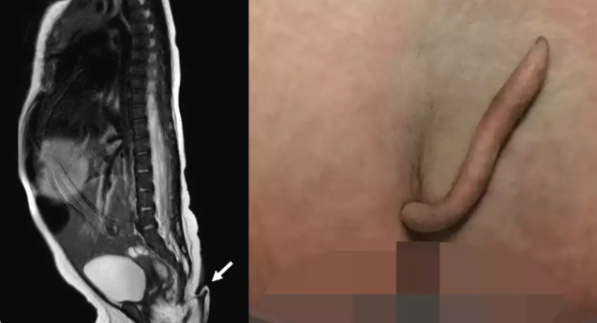

Bé gái chào đời với chiếc đuôi dài 5 cm cực hiếm. Tại Mexico. một bé gái sinh ra với chiếc "đuôi thật" dài 5 cm, mềm, bao phủ bằng một lớp da và lông mịn và có một đầu hơi nhọn.

Điều đặc biệt khiến cha mẹ, bác sĩ đều kinh ngạc chính là chiếc đuôi nhỏ của bé gái khi mới chào đời. Cái đuôi nhô ra ở cuối xương cụt với phần gốc hơi lệch về bên trái.

Chiếc đuôi dài 5 cm, mềm, bao phủ bằng một lớp da và lông mịn và có một đầu hơi nhọn. Đường kính thay đổi từ 3 mm đến 5 mm, thu hẹp dần về phía đầu nhọn.

Bác sĩ Josue Rueda đứng đầu ca mổ cho biết đây là trường hợp đầu tiên ghi nhận ở Mexico. Hiện tượng hiếm gặp chỉ xuất hiện ở khoảng 200 ca. Em bé chào đời đủ tháng và không có biến chứng nào trong thai kỳ. Cấu trúc mềm, có phần da bao phủ và lông mịn, có thể di chuyển thụ động mà không gây đau đớn. Đứa bé đã khóc khi bác sĩ thử đâm nhẹ vào phần đuôi.

Cha mẹ bé gái đã có một cậu con trai khỏe mạnh trước đó. Đứa trẻ sơ sinh khỏe mạnh, các xét nghiệm về não, tim, thính giác và nước tiểu cho kết quả bình thường. Khi bé gái được hai tháng tuổi, các bác sĩ tiến hành cắt bỏ chiếc đuôi. Chiếc đuôi có chứa cơ, mạch máu, dây thần kinh nhưng không có xương. Kết quả kiểm tra cho thấy cái đuôi không phải là hậu quả của vấn đề liên quan đến cột sống.